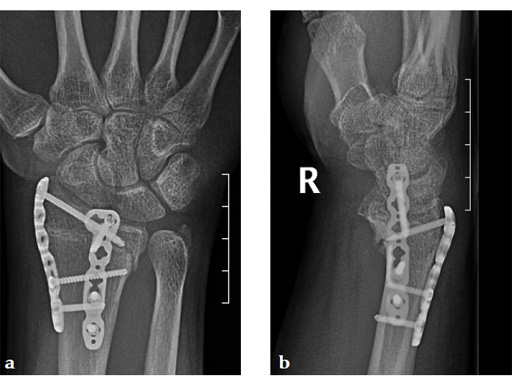

Case 2: A 44-year-old man sustained polytrauma following a car accident. Among his injuries was a distal radial fracture, Mller AO Classification 23-C1.

Case provided by Vitezslav Ruber, Brno, Czech Republic